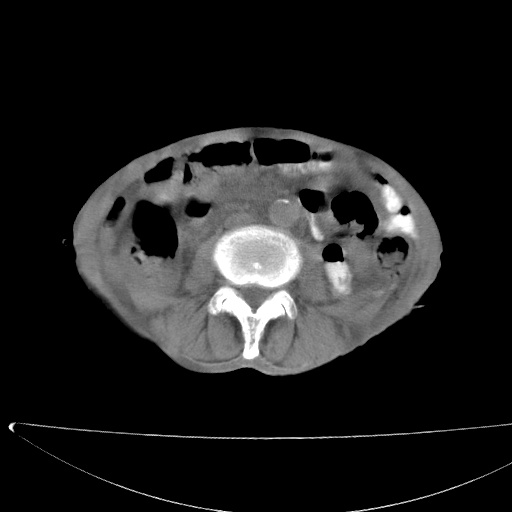

患者男70岁,上腹部不适1月。8年前有胃癌手术史。余病史不祥。

考虑胃癌复发并小网膜淋巴结转移侵及肝脏胆总管梗阻

考虑胃癌复发并腹腔内淋巴结转移。

1)胃癌术后,复发不排除。

2)肝脏转移瘤。

3)肝脏钙化灶。

4)胆囊增大。

5)腹膜后多发性淋巴结转移。

6)腹水。

建议:增强扫描。

考虑胃窦癌肝门转移

考虑胃癌复发并腹腔内淋巴结转移,胆总管受侵。

考虑胃窦癌肝门区淋巴结转移!

1)胃癌术后,不排除复发可能。2)考虑肝脏及腹膜后淋巴结转移瘤。3)肝内胆管扩张,胆囊增大。4)肝内胆管结石(或钙化)。5)脾脏钙化灶。6)腹水。7)右侧少量胸腔积液。

建议:行ct增强扫描检查。

1、胃癌根治胃空肠吻合术后,残胃癌?

2、肝门区占位性病变并胆道上段梗阻(肝内胆管扩张、胆囊增大),考虑肝门区淋巴结转移累及胆总管,建议ct增强扫描;

3、右侧胸腔少量积液、少量腹水;

4、肝右叶胆管结石。

肝门区占位性病变并肝内胆管扩张。

小网膜囊区及腹膜后肿大淋巴结。